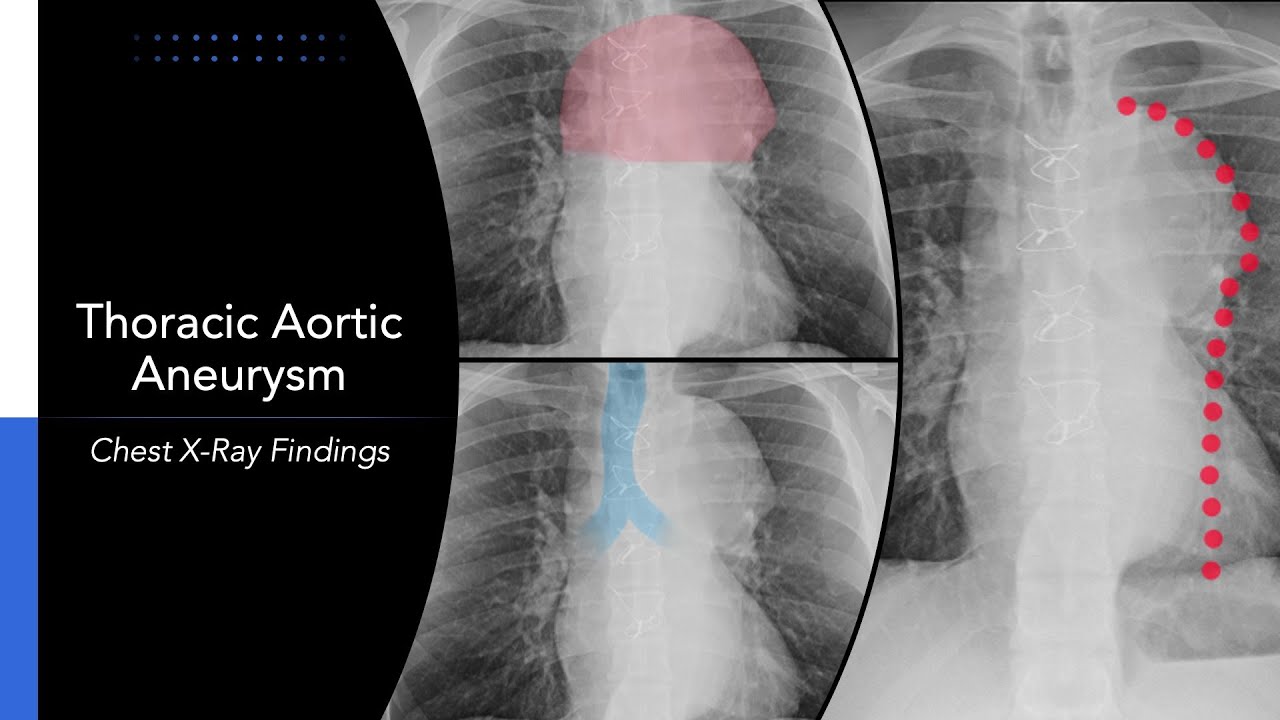

Thoracic Aortic Aneurysm Chest X Ray Shorts

Aortic Aneurysm On Chest X Ray Hot Sex Picture Thoracic aortic dissection occurs s clinical presentation and symptoms Chest x-ray can show mediastinal widening and/or an abnormal aortic contour Computed tomography (CT) is the definitive

Thoracic Aortic Aneurysm Radiology Cases